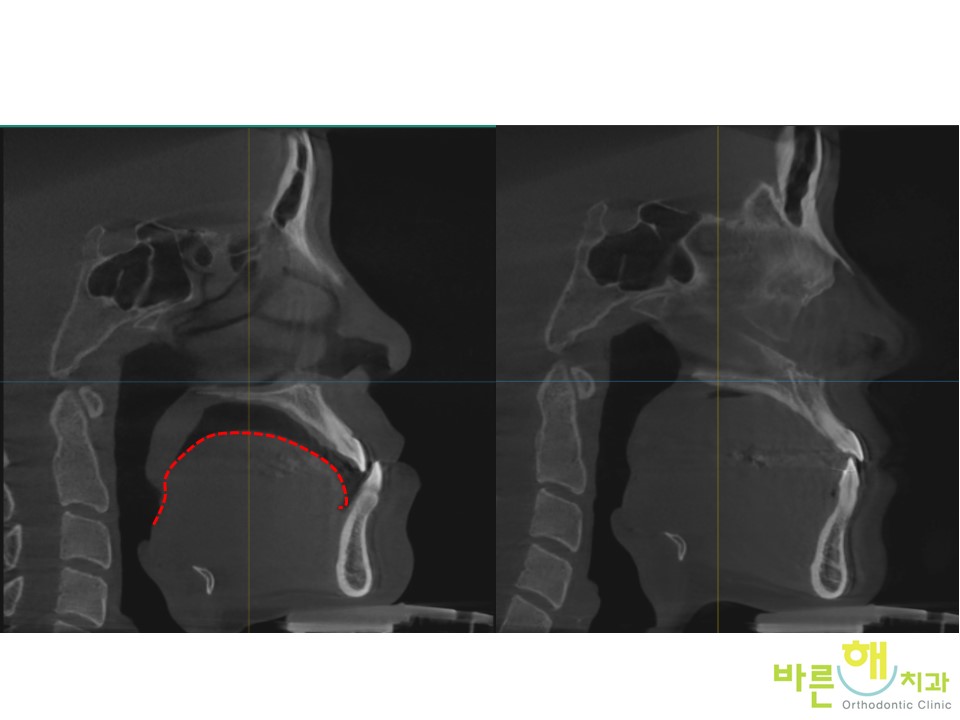

ÀÌ·± »óÅ¿¡¼­

´Ã ÀÔ¼úÀ» ´Ù¹°°í

ÄÚ·Î ¼ûÀ» ½¬°í

¹Ù¸£°Ô ¿¬Çϸ¦ ÇÏ´Â

Ä¡¾Æ¿Í °ü·ÃµÈ ÁÁÀº ±â´ÉÀÌ

Àß Çü¼ºµÇ¾î ÀÖ´Â °ÍÀÌ Áß¿äÇÕ´Ï´Ù.

±×·¡¾ß

ºñ¼ö¼ú ÁÖ°ÆÅÎ ±³Á¤Ä¡·á°¡ ³¡³­ ÈÄ¿¡

½Ã°£ÀÌ °æ°úÇØµµ

ÁÁÀº ±³ÇÕÀÌ Àß À¯ÁöµÉ ¼ö Àֱ⠶§¹®ÀÔ´Ï´Ù.

ºñ¼ö¼ú ÁÖ°ÆÅÎ ±³Á¤Ä¡·á ÀüÈÄ

Ä¡¾Æ °Ç°­»óÅ´ ¹°·Ð ¾çÈ£ÇÕ´Ï´Ù.

´Ã Çô°¡ ÀÔõÀå¿¡ ºÙ¾î ÀÖ´Â °ÍÀÌ Áß¿äÇÕ´Ï´Ù.